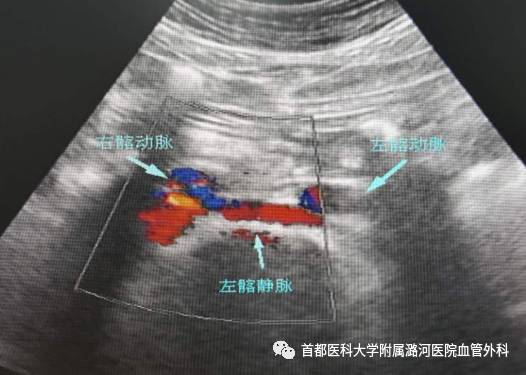

彩色多普勒超声

左侧髂静脉受压处管腔变扁,前后径变小。受压的远端扩张,呈“喇叭口”状改变。常伴髂静脉腔内血栓形成,长期血栓可形成大量侧支循环。

直接征像:

受压狭窄区域呈“五彩镶嵌”持续性高速血流;严重受压时受压处血流可缓慢,通过挤压肢体远端可见血流通过;完全闭塞时彩色血流信号中断。

间接征像:

受压远心端侧支循环形成,如髂内静脉血流反向,盆腔内静脉曲张等;髂外静脉呼吸相减弱,甚至消失。

正常髂静脉超声